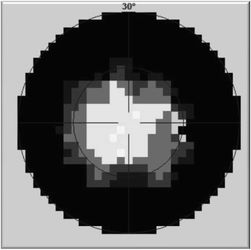

Vyšetření statickým počítačovým perimetrem - zorné pole před

Vyšetření statickým počítačovým perimetrem - zorné pole po

U druhé pacientky B.J., nar. 1974 trvala konstrikce zorného pole

na 10 až 20 st. 5 let, v průběhu kterých prodělala opakovaně náročná

vyšetření, marně hledající příčinu zúžení. K rozšíření zorného pole

došlo spontánně v 18 letech věku nemocné. Rozšíření si dáváme do

souvislosti s nabytím určité svobody a volnosti, ve které byla dříve

přísně omezována.